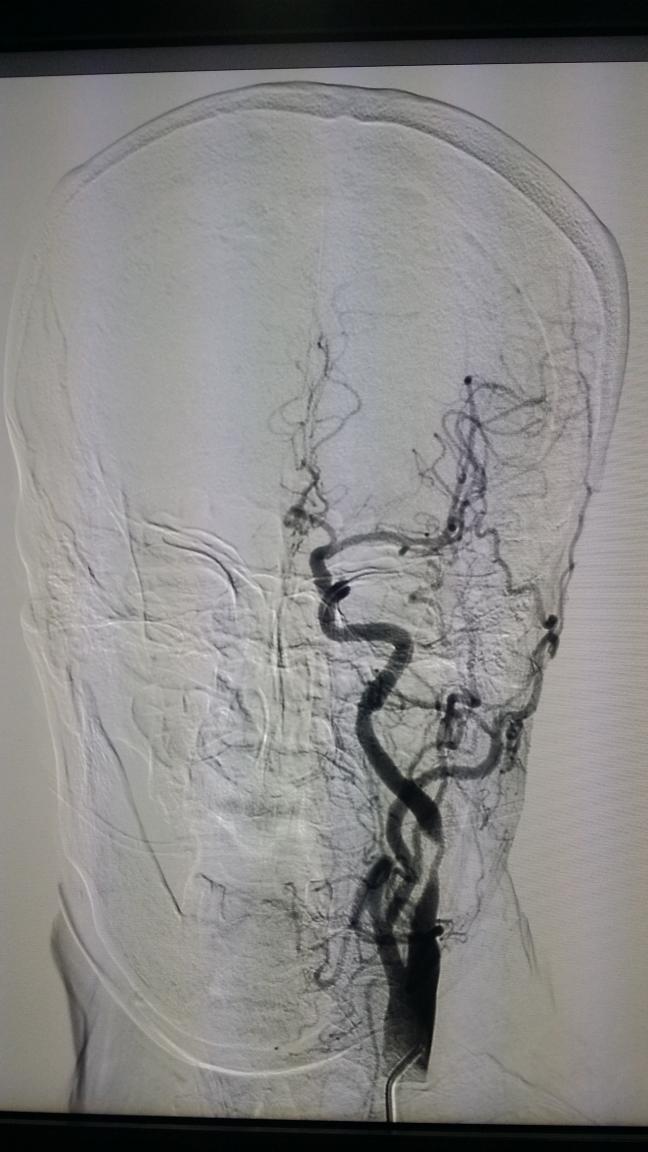

颈动脉支架手术示例:

正位: 术前 支架植入后

侧位: 术前 支架植入后